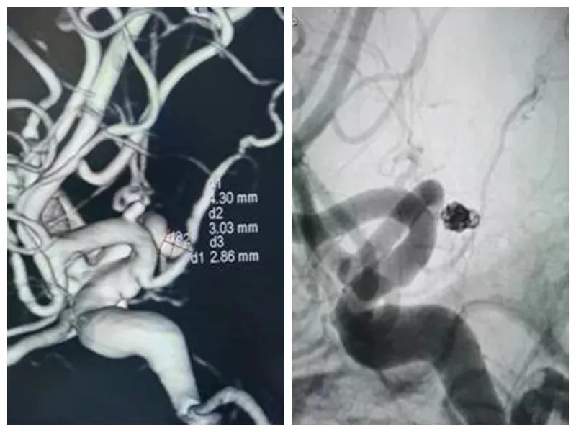

一、技术能力:收治所有神经系统疾病,目前常规诊治的疾病有:脑梗死、脑出血、蛛网膜下腔出血、慢性脑供血不足、头晕、头痛、三叉神经痛及中枢神经系统感染(各种脑炎)、癫痫、帕金森病、周围神经病、老年痴呆、失眠等各种神经系统疾病。二、科室特色:在2007年创先开展急性脑梗超早期溶栓治疗并取得可喜成果,不少生命垂危的病人经积极溶栓治疗后得到较好的治疗效果,对急性脑出血的处理上也有独到的经验。在2018年成立卒中中心,由多学科联合组成的脑血管病诊断治疗快速反应小组,为急性脑血管疾病患者开通了绿色通道,为脑血管疾病患者治疗争取宝贵时间。2019年12月顺利通过国家级卒中中心评审。2020年引进数字减影血管造影X线机,内二科已常规开展脑血管造影,脑梗死取栓,颅内动脉瘤填塞,脑血管支架植入等手术。

三、主要设备:数字减影血管造影(DSA)、1.5T双引擎磁共振、320排CT、数字减影血管造影X线机、常规脑电图、24小时动态脑电图、肌电图、诱发电位,经颅多普勒(TCD)、脑脊液检查、基因检测等。四、科室电话:0792-2779527(内线5197)